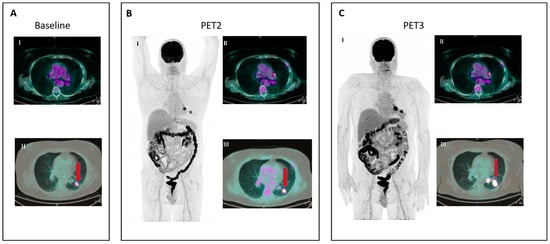

- IR(2): Appearance of new lesions in the context of overall TB stability (Figure 2).